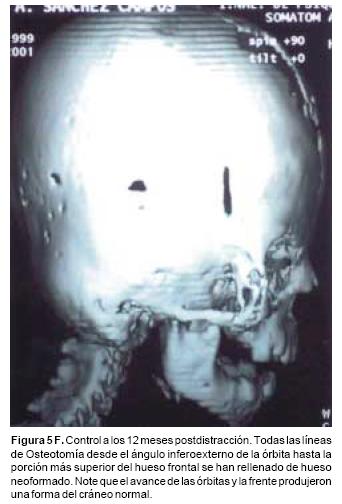

Luego de un periodo de latencia de cinco días, los distractores se activan a un ritmo de un milímetro cada día. Los avances obtenidos en este grupo de pacientes varían entre 16 y 30 mm, en el hueso frontal, de 12 a 25 mm, en el complejo órbito–malar–cigoma y de 10 a 18mm, en el maxilar. Luego de un periodo de consolidación de 10 a 12 semanas, los distractores óseos se retiran bajo sedación.

En todos los pacientes se logró el avance planificado de los segmentos óseos, al corregir la deformidad del hueso frontal, el exorbitismo y en la retrusión del tercio medio en los casos con avance en monobloque. Los avances mayores se obtuvieron en el hueso frontal y variaron entre 16 y 30 mm., mientras que los menores fueron los del hueso maxilar que fluctuaron entre 9 y 16 mm. (Cuadro I). Radiológicamente los controles postoperatorios tempranos mostraron inicialmente áreas de hipodensidad ósea, que al final del periodo de consolidación cambiaron a áreas de densidad ósea radiológica normal, lo que significa neoformación de hueso. Las áreas de hueso neoformadas que consolidaron en forma más rápida, son las ubicadas en las líneas de osteotomía de la unión pterigomaxilar, pared lateral de la órbita y unión frontoorbitaria. Las áreas que más tardaron en consolidar incluye la porción lateral y superior del hueso frontal.

También los controles radiológicos durante el proceso de distracción mostraron que no se produjo la creación de espacios muertos intracraneanos durante los avances. En todos los pacientes con sinostosis bicoronal el avance frontoorbitario produjo excelentes resultados estéticos dando una nueva forma a la región frontal y proyectando mejor el reborde supraorbitario. En los niños con enfermedad de Crouzon y síndrome de Apert, se corrigió en forma muy satisfactoria el exorbitismo al resolver las graves exposiciones corneales (Figuras 5 A, B, C, D, E, F, G, H), en los que se utilizó el avance simultáneo del tercio medio, este cambio óseo corrigió muy satisfactoriamente la retrusión del mismo, ampliando la vía aérea y resolviendo en muchos casos grandes problemas ventilatorios durante el sueño (Figuras 6 A, B, C, D, E, F). Los pacientes con plagiocefalia corrigieron significativamente la deformidad frontoorbitaria y los tejidos blandos suprayacentes se adaptaron a la nueva estructura ósea. La clásica órbita de arlequín de estos niños producida por la sinostosis del frontal con el esfenoides, inmediatamente se ve corregida en su forma y su configuración se hace muy similar con la órbita contralateral (Figura 7)(Fig. 7a, 7b, 7c, 7d, 7e, 7f, 7g) (Cuadro II).